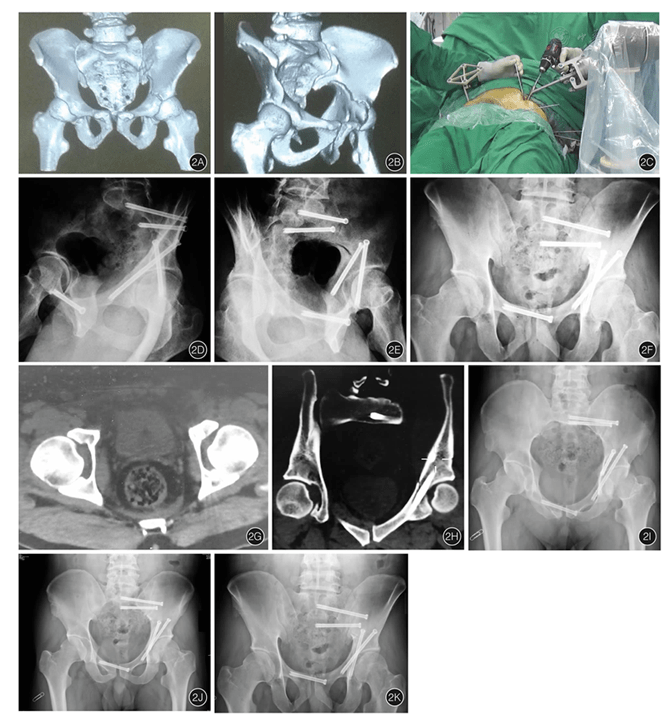

春立医疗董秘:尊敬的投资者,您好!公司积极布局医疗器械科技前沿领域,目前,髋关节手术机器人、膝关节手术机器人、单髁手术机器人等产品均已获得对应注册证。公司将持续融合创新技术,驱动产品迭代与性能突破。感谢您的关注!